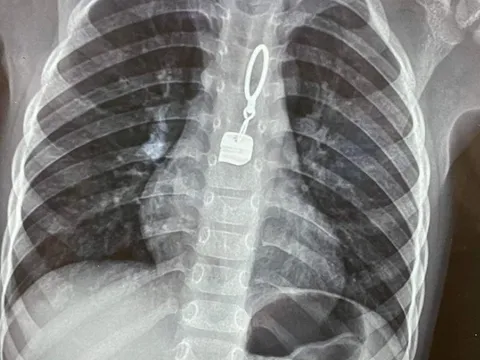

Phát hiện kim khâu quần áo nằm trong phổi bé trai 4 tuổi

Sau khi chụp Xquang, các bác sĩ phát hiện trong phổi trái bé trai 4 tuổi có dị vật hình dạng kim may quần áo.